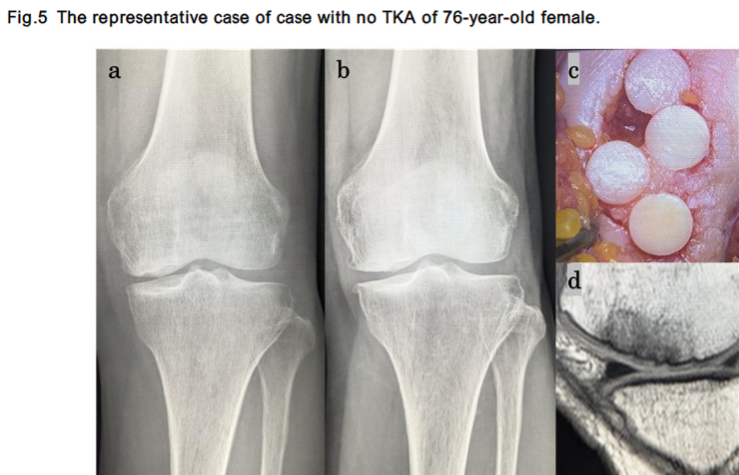

The changes in X-ray findings, intraoperative findings, and MRI findings are shown for two representative cases.